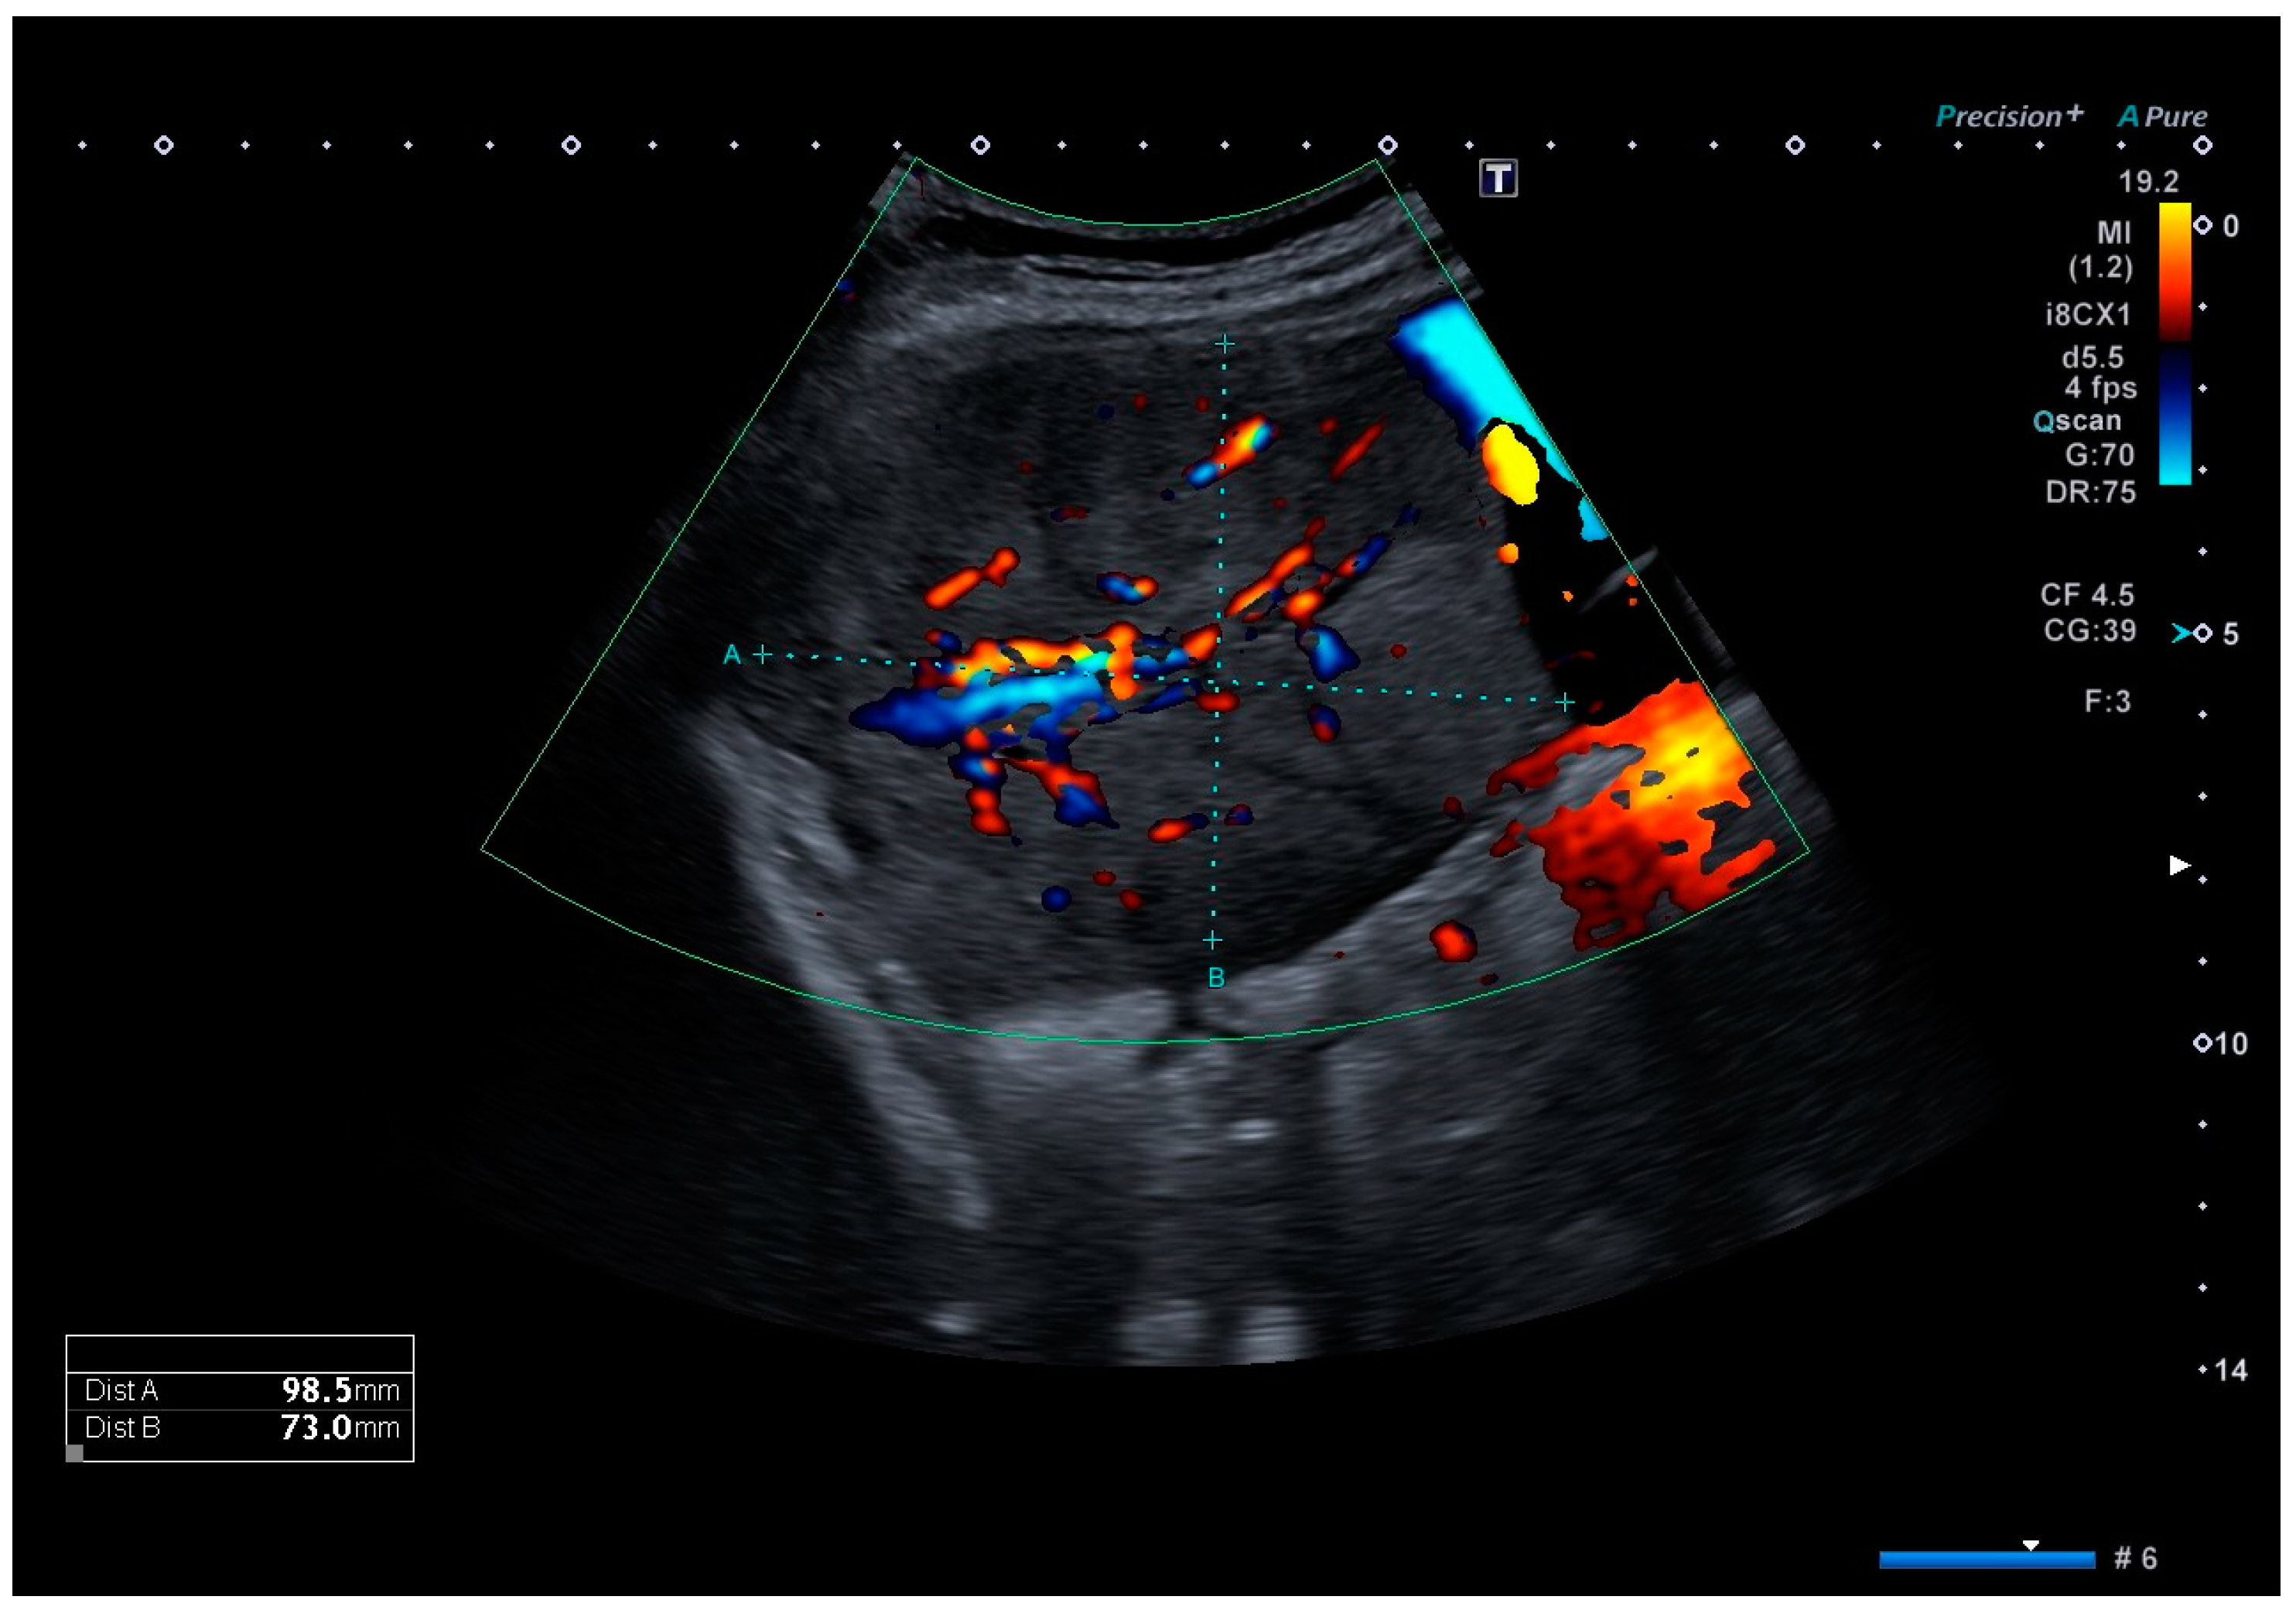

Clinical examination upon admission showed a completely asymptomatic patient. Ultrasound imaging showed a timely developed singleton pregnancy, and an invasive placental growth seemed unlikely as the intrauterine placentation showed no sonomorphological placenta accreta spectrum abnormalities. However, in the right middle abdomen, adjacent to the uterine wall, a well-definable, echo-dense tumor of 99 × 73 × 75 mm in size could be detected, with surrounding ascites, which is shown in Figure 1. A comparable structure was also displayed on the left side, measuring 70 × 34 × 37 mm, most likely originating from the left adnexa. Both lesions showed an area with increased vascularization. Sonographically, offering a definite diagnosis was not possible, but the initial diagnosis of placenta percreta was reassigned as adnexal tumors, possibly chorion tumors.

Figure 1.

Color Doppler ultrasound image of the tumor located in the right middle abdomen, depicting a moderate vascular flow. The tumor is embedded in ascites.